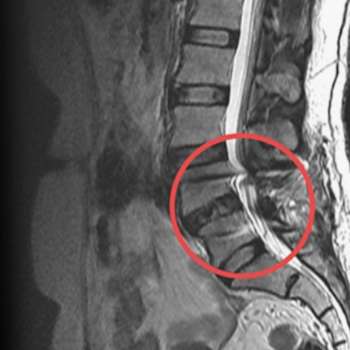

척추관 협착증(Spinal stenosis)은 척추관이 좁아져 척수와 신경을 압박하는 상태로, 주로 중년 이후에 발생하지만 다양한 원인으로 인해 젊은 연령층에서도 발생할 수 있습니다. 전문가의 입장에서 척추관 협착증의 주요 원인 10가지를 상세히 설명하겠습니다.

디스크 탈출증은 디스크의 중심부가 파열되어 외부로 밀려 나오는 상태입니다. 탈출된 디스크가 척추관을 좁히고 신경을 압박하여 척추관 협착증을 유발할 수 있습니다. 디스크 탈출증은 주로 허리 디스크(요추 디스크)에서 발생하며, 이는 척추관 협착증의 중요한 원인 중 하나입니다. 또한, 외상이나 무거운 물건을 들다가 생길 수 있는 급성 손상으로 인해 디스크가 탈출할 수도 있습니다.